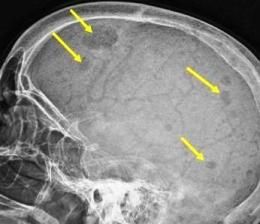

A 92-year-old woman presented with a 6-month history of progressively worsening fatigue, weight loss, generalized bone pain, and dyspnea on exertion. A skeletal survey found lytic lesions in the pelvis, sacrum, and calvarium (shown here).

Laboratory studies found normocytic anemia (hemoglobin 5.6 g/dL and hematocrit 17.3%); hypoalbuminemia (albumin 1.9 g/dL); elevated total protein, 9.8 g/dL (normal range, 6.3 to 8.2 g/dL); and serum creatinine, 15.5 mg/dL. Corrected serum calcium was 10.1 mg/dL (normal range, 8.4 to 10.2 mg/dL). A skeletal survey found lytic lesions in the pelvis, sacrum, and calvarium (Figure). Serum protein electrophoresis (SPEP) showed abnormal bands in the gamma region (4.8 g/dL). Serum free light chain revealed an abnormal kappa/lambda ratio (0.7:16.2). Serum immunofixation demonstrated IgA/lambda monoclonal protein, and a diagnosis of IgA/lambda multiple myeloma (MM) was made.

The characteristic findings on bone survey are multiple ‘‘punched-out’’ lytic lesions within the axial bone, such as skull, vertebral bodies, pelvis, or upper part of the extremities as seen in our case.4 Renal involvement is usually divided into 3 categories: